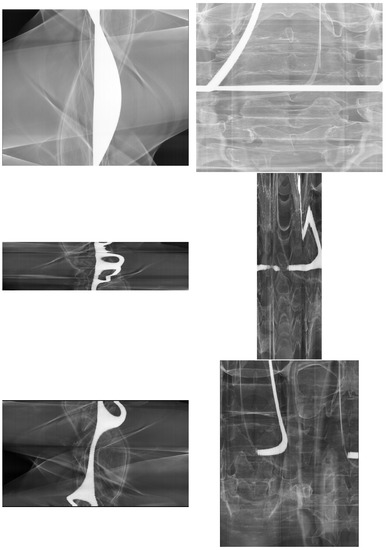

2.4. Image Data